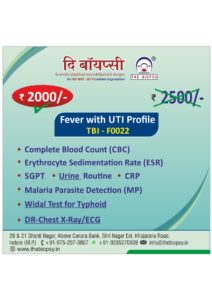

Our Health Packages

We Provide All Types of Diagnostics Services and its Health Pacakages also.